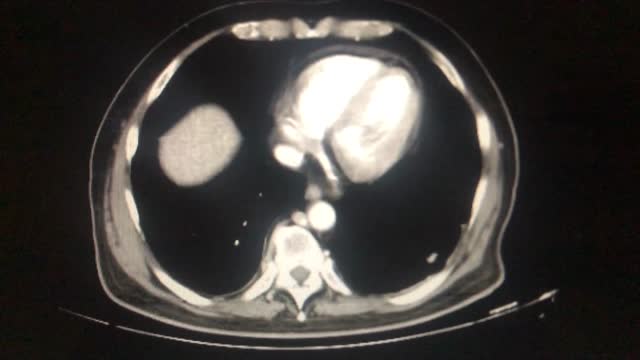

Técnica quirúrgicaPaciente varón de 55 años que consulta por molestias en fosa renal derecha asociado a síndrome constitucional con pérdida de 10kg de peso en los últimos dos meses y disnea a mínimos esfuerzos. La TAC mostró una masa renal izquierda de gran tamaño (15 x 13 x 11cm), que desestructura el riñón, llegando al hilio renal con una imagen de trombosis de la vena renal que continua con trombosis de la vena cava inferior, trombosis de la parte distal de la vena renal izquierda y trombosis hasta la región íleo femoral (estadio IIIB, según clasificación de Ciancio et al.17). El caso se presentó en el Comité Oncológico y se decidió intervención de la masa renal con colaboración por parte de cirujanos hepatobiliares y cirujanos cardiovasculares. Urología realizó la resección de la masa renal de forma solitaria, dada la imposibilidad de extirpar en bloque toda la pieza tumoral. Cirugía realizó liberación de los ligamentos hepáticos derechos e izquierdos, disección, ligadura y sección de venas retrohepáticas para exponer la VCI en toda su extensión, hasta la salida de las VSH. La VCI suprahepática fue disecada y rodeada mediante un lazo vascular para control por si fuera necesario. Se confirmó mediante clampaje por debajo de la desembocadura de las VSH un adecuado drenaje hepático y sistémico. Los cirujanos cardiovasculares realizaron la exéresis de la VCI hasta la bifurcación de las iliacas, previa ligadura de vena renal izquierda. La longitud de la vena resecada no permitió la reconstrucción de la misma. Al recolocar el hígado en la fosa hepática se produjo un descenso y desplazamiento craneal del hígado por ausencia de la tumoración y la cava trombosada ya resecadas, lo que provocó el cierre del drenaje venoso de las VSH, conllevando inestabilidad hemodinámica y congestión hepática (coloración azulada, aumento de volumen y consistencia del hígado). Por dicho motivo se avisó a los cirujanos hepáticos, quienes al revisar valoraron que el descenso en la fosa hepática del hígado era responsable de la situación de inestabilidad. Por ello se colocó una prótesis de silicona para elevar el hígado; sin embargo, el desplazamiento craneal del mismo hacia el diafragma mantenía la dificultad de drenaje venoso de éste y la situación de inestabilidad. Se decidió colocar una segunda prótesis para mantenerlo en su posición y evitar su desplazamiento hacia el diafragma. Esto permitió que el drenaje venoso fuera adecuado, el hígado mejoró de su congestión y desapareció el estado de inestabilidad. No se realizó flujometría ni ecodoppler por ausencia de disponibilidad de aparataje. Durante su estancia en UCI preciso hemodiálisis por insuficiencia renal aguda y presentó un tromboembolismo pulmonar. En TAC de control postoperatorio se objetivó una correcta posición con ambas prótesis, buen drenaje venoso y adecuada perfusión hepática. La histología fue de carcinoma de células claras, grado 4 de la Organización Mundial de la Salud/International Society of Urological Pathology (OMS/ISUP), con extensas áreas sarcomatoides (> 50%) y cava inferior con ocupación de luz por carcinoma e infiltración de la pared, así como afectación de la glándula suprarrenal (T4N0Mx).